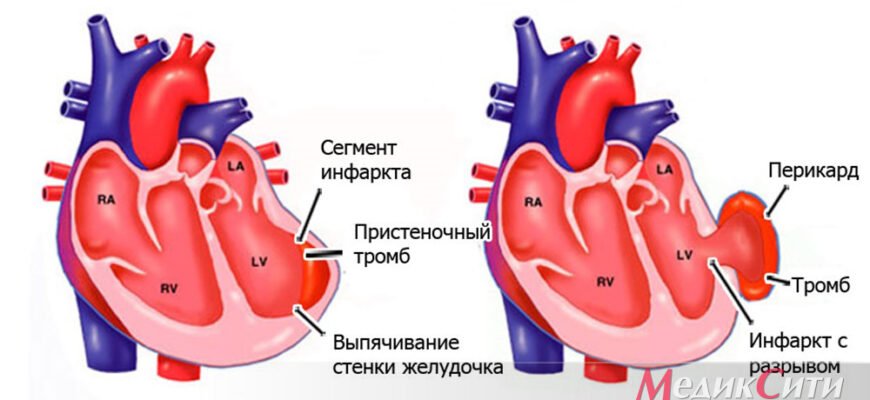

Аневризма серця: неминучі виклики та підводні камені Що таке аневризма серця? Аневризма серця — це такий собі підступний ворог, здатний тихо і без попереджень зачаїтись.